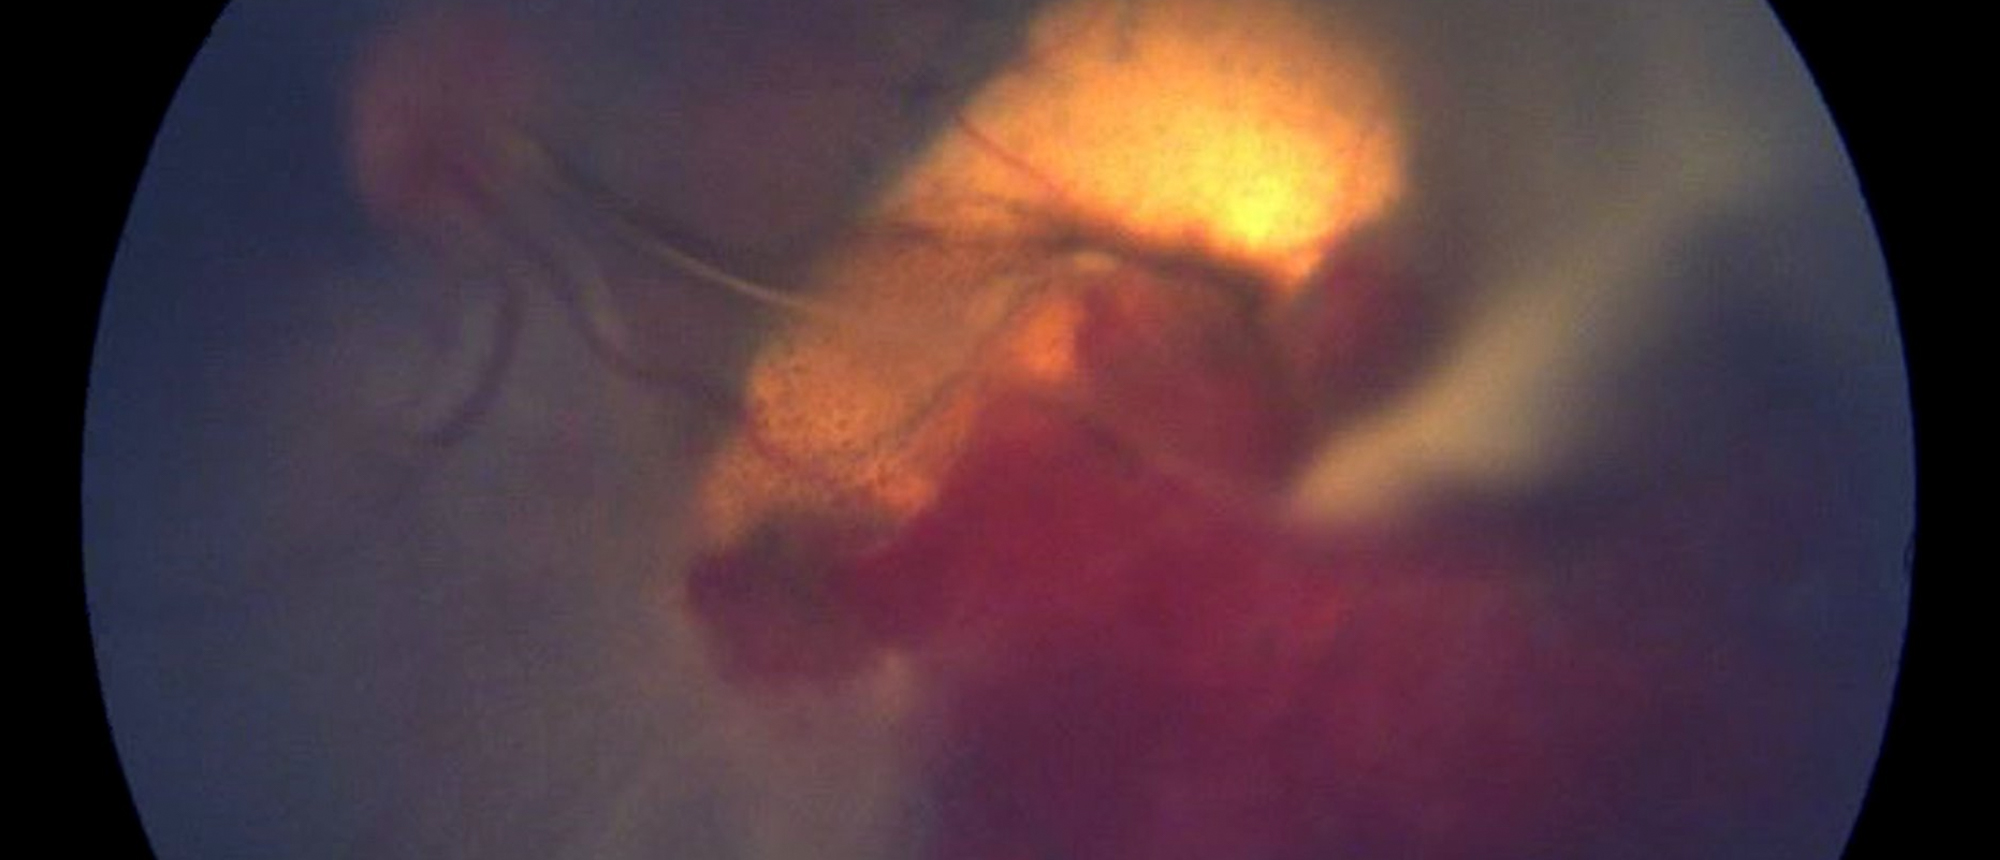

Melanocytoma with Vitreous Seeding

Specialty: Corneal and External Diseases

Include in Catalogue?: No

Presenter(s): Nathan L. Scott, MD, MPP

Faculty Discussant(s): Zelia M. Correa, MD, PhD; Sander R. Dubovy, MD

Melanocytoma with Vitreous Seeding A patient with 7 years of blurry vision in the right eye presents to clinic for evaluation. He reports no recent acute changes in vision and no precipitating events in the past. He noticed the blurry vision incidentally while driving when he covered his left eye. …

Specialty: Ocular Oncology

Type: Online Grand Rounds

Include in Catalogue?: Yes

Presenter/Faculty: Correa, Dubovy, Scott